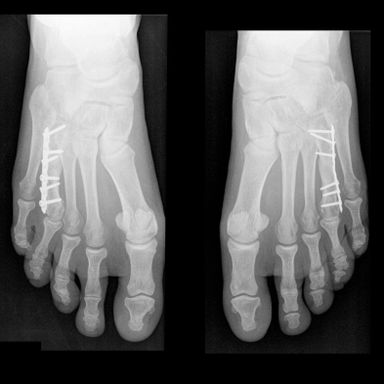

两个小夹板保护新形成的跖骨。